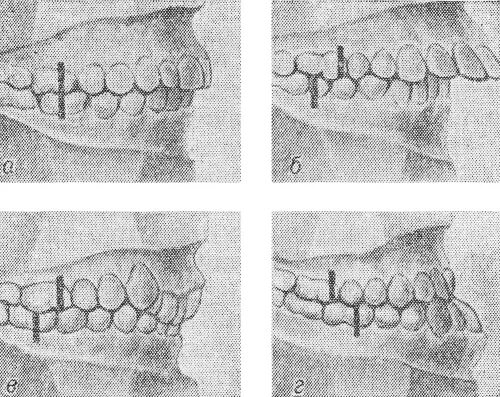

Сагиттальные аномалии окклюзии